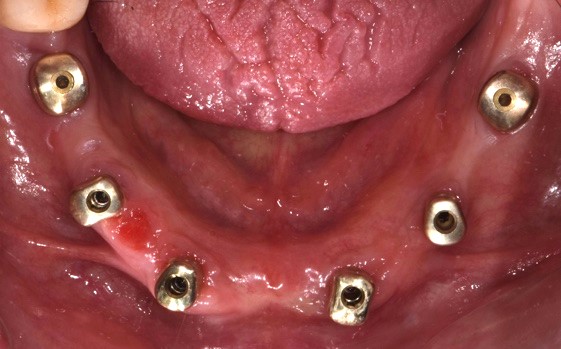

Durante l'intervento chirurgico si posizionava la guida (Fig. 3a) e i siti implantari venivano fresati secondo le sequenze previste. Posizionavamo gli impianti (LYRA ETK, Sallanches, Francia) e gli abutment iPhysio® Profile Designer (Fig. 3 b) che erano selezionati in base al profilo di emergenza desiderato del futuro restauro.

Questi healing abutments vengono avvitati sugli impianti durante la prima o la seconda fase chirurgica. Essi poi restano in posizione durante tutta la guarigione ossea e gengivale e durante la presa dell'impronta, indipendentemente dall'area di impianto. Il Profile Designer iPhysio® viene essere rimosso solo una volta, per posizionare il restauro finale. Gli abutment provvisori in polieter-eter-chetone (PEEK) venivano agganciati agli iPhysio® Profile Designers, sui quali venivano adattati i restauri provvisori (Fig. 3c). Il carico immediato degli impianti è stato eseguito utilizzando una protesi provvisoria in PMMA (Fig. 3d). Al rientro per un controllo, si osservava una corretta guarigione dei tessuti attorno agli impianti e attorno agli abutment iPhysio®.

Fotografia degli impianti appena inseriti con iPhysio® avvitati

Fig. 3(b) Fotografia degli impianti appena inseriti con iPhysio® avvitati.

Si procedeva quindi alla scansione degli iPhysio® utilizzando uno scanner intraorale (IS 3600®, Dexis, Envista Holding Corporation, Brea, USA) (Fig. 4 a). Inviavamo i file STL al laboratorio odontotecnico per progettare e realizzare la protesi finale (Fig. 4 b,c,d,e,f).